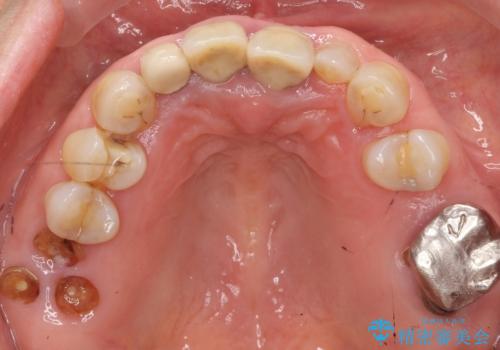

- ¥1,010,000 (仮歯×9本、ファイバーコア×1本、ジルコニアクラウン スタンダード×9本)費用は治療当時の料金となります

自然な仕上がりと使い心地に喜んで頂けました。

奥歯の治療もやりたいとおっしゃって下さり、今後進めていく予定です。

ジルコニアクラウン スタンダード